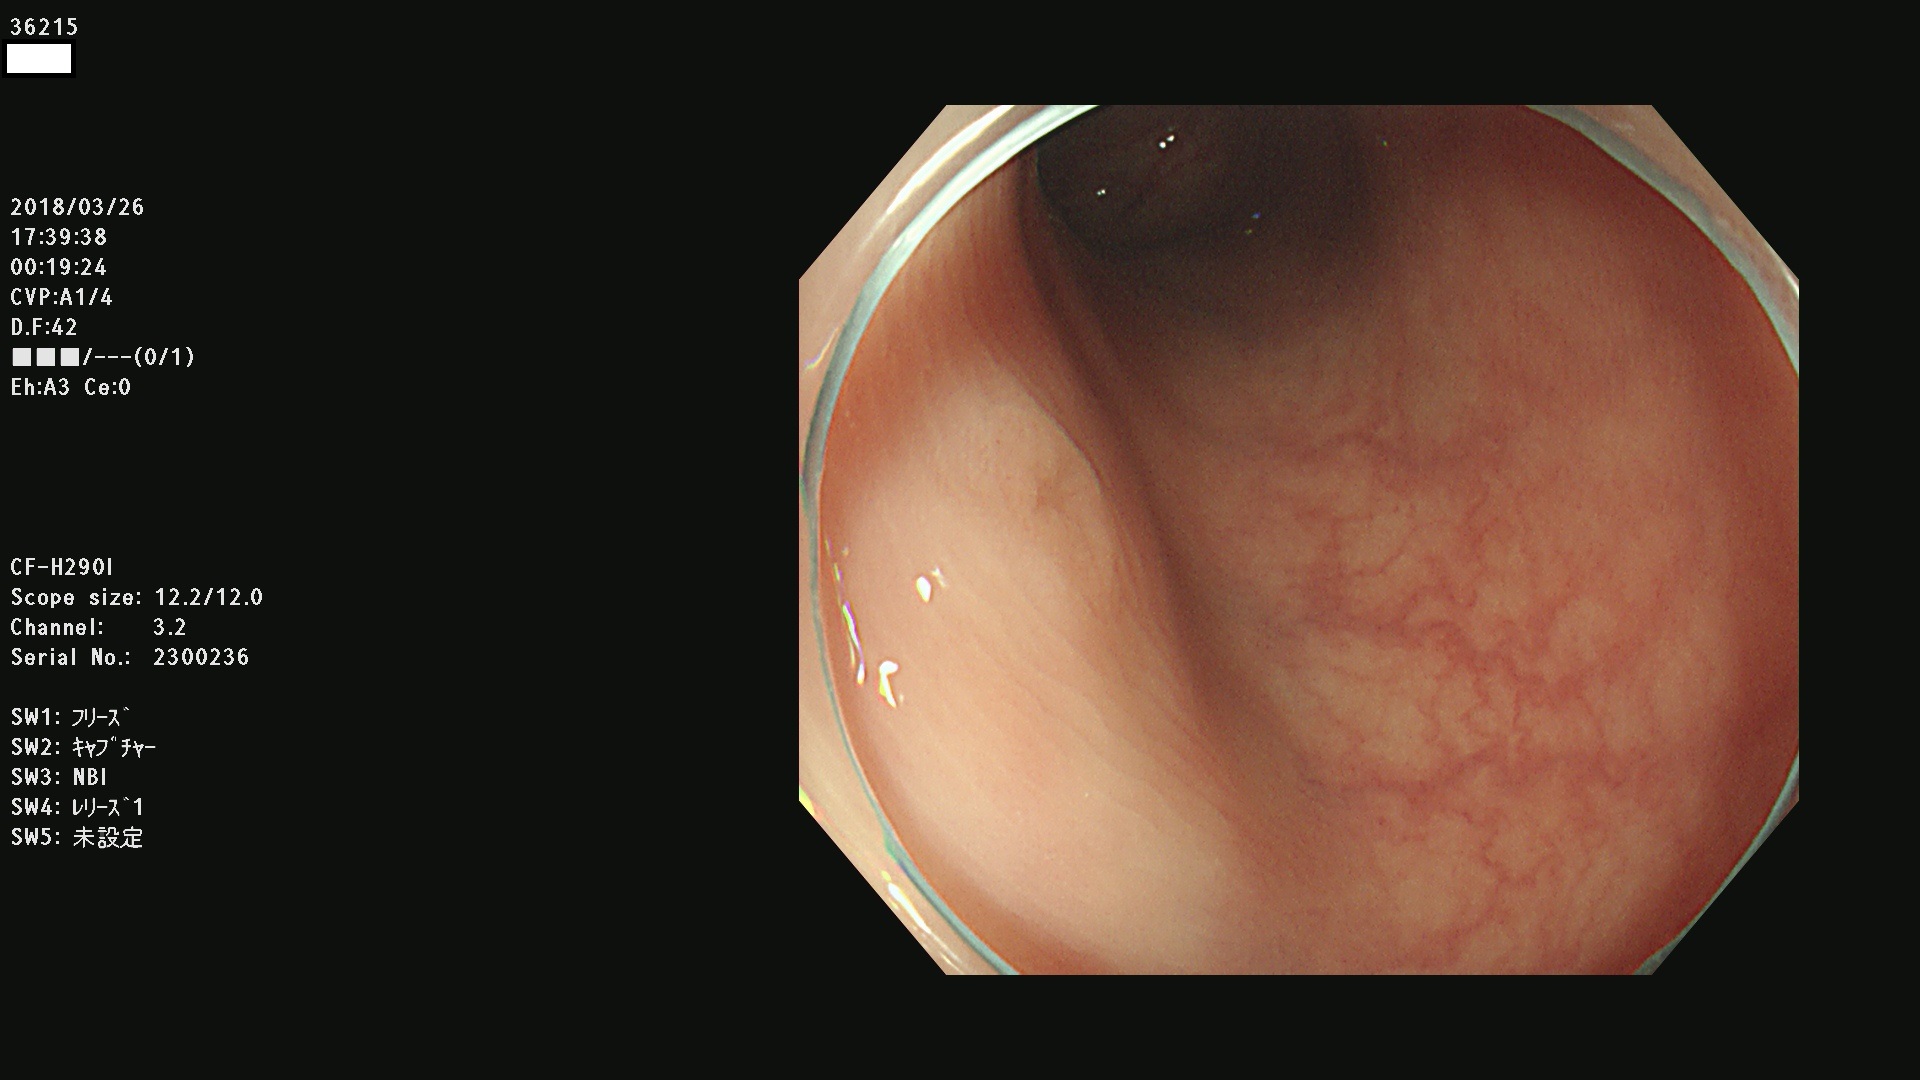

36201 36202 36203 36205 36207 36209 36210 36212 36213 36214 36215 36217 36220 36221 36222 36224 36225 36226 36227 36229 36230 36231 36232 36235 36236 36238 36240 36243 36244 36246 36247(SSAPのみ。SPS) 36248 36249 36251 36252 36253 36254 36255 36256 36257 36258 36259 36261 36262 36264 36265 36267 36269 36270 36272 36274 36275 36276 36279 36280 36281 36283 36285 36288 36289 36291 36292 36295 36296 36297 36299

発見困難で危険性の高い平坦型病変(上記100名より抽出)